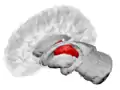

![]() Thalamus marked (MRI cross-section) | |

The thalamus (pl.: thalami; from Greek θάλαμος, "chamber")[1] is a large mass of gray matter located in the dorsal part of the diencephalon (a division of the forebrain). Nerve fibers project out of the thalamus to the cerebral cortex in all directions, known as the thalamocortical radiations, allowing hub-like exchanges of information. It has several functions, such as the relaying of sensory signals, including motor signals to the cerebral cortex[2][3] and the regulation of consciousness, sleep, and alertness.[4]

Anatomically, it is a paramedian symmetrical structure of two halves (left and right), within the vertebrate brain, situated between the cerebral cortex and the midbrain. It forms during embryonic development as the main product of the diencephalon, as first recognized by the Swiss embryologist and anatomist Wilhelm His Sr. in 1893.[5]

The thalamus is a paired structure of gray matter about four centimetres long, located in the forebrain which is superior to the midbrain, near the center of the brain with nerve fibers projecting out to the cerebral cortex in all directions. The medial surface of the thalamus constitutes the upper part of the lateral wall of the third ventricle, and is connected to the corresponding surface of the opposite thalamus by a flattened gray band, the interthalamic adhesion. The lateral part of the thalamus is the phylogenetically newest part of the thalamus (neothalamus), and includes the lateral nuclei, the pulvinar and the medial and lateral geniculate nuclei.[6][7] There are areas of white matter in the thalamus including the stratum zonale that covers the dorsal surface and the external and internal medullary laminae. The external lamina covers the lateral surface and the internal lamina divides the nuclei into anterior, medial, and lateral groups.[8]